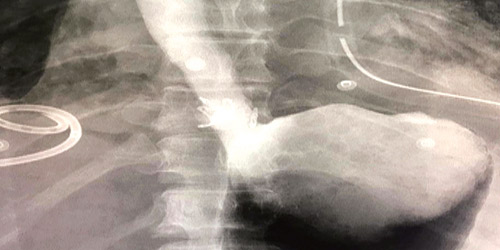

وقد قام الفريق الطبي بالتنسيق مع فريق التخدير بتحضير الحالة لغرفة العمليات، ووضعها تحت البنج الكامل، وتم التدخل بالمناظير غير الجراحية، وتركيب دعامات المريء، وقفل الثقب باستخدام لاقطات المنظار الحديثة (OVESCO). كما تم التأكد من إقفال جميع طبقات جدار المريء، ووضع دعامات معدنية، وكذلك عمل الصبغة تحت الأشعة، إضافة إلى السيطرة على الالتهاب في التجويف الصدري بالتدخل الجراحي الصدري. وقد استمرت العملية ساعتين، وتكللت - ولله الحمد - بالنجاح. وتم بعدها نقل الحالة إلى غرفة العناية المركزة ثم إلى قسم التنويم حتى تماثلت الحالة للشفاء، وتم خروجها وهي بأتم الصحة والعافية.